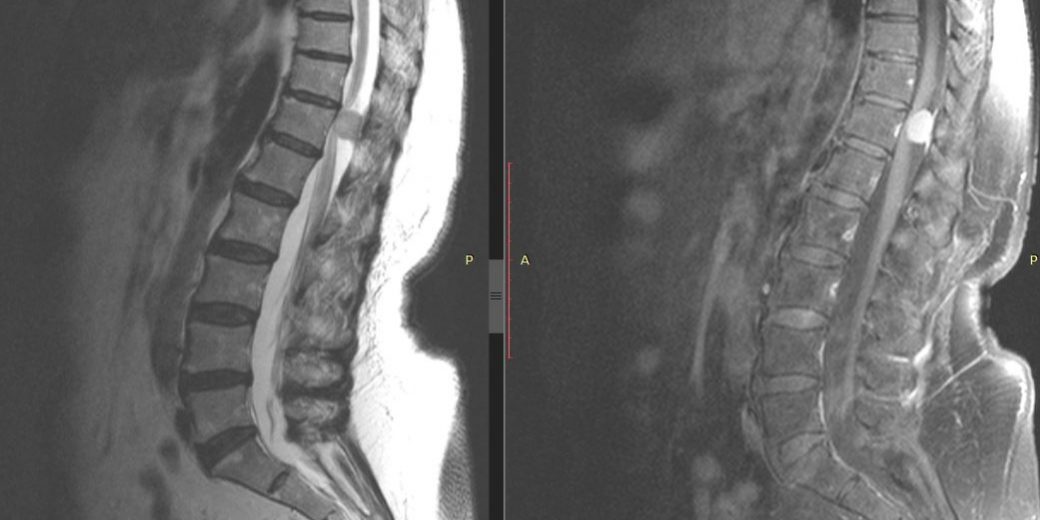

Ο έλεγχος με μαγνητική τομογραφία με σκιαγραφικό ανέδειξε μηνιγγίωμα όπισθεν του Θ12 σπονδύλου, με σημαντική πίεση επί των νευρικών στοιχείων.

Η μετεγχειρητική πορεία ήταν ανεπίπλεκτη με άμεση βελτίωση τόσο του πόνου όσο και της μυικής ισχύος και βάδισης της ασθενούς. Ο μετεγχειρητικός έλεγχος 3μήνου με μαγνητική τομογραφία αναδεικνύει την ολική εξαίρεση του μηνιγγιώματος αλλά και το εξαιρετικά περιορισμένο χειρουργικό τραύμα, λόγω της πεταλοπλαστικής.